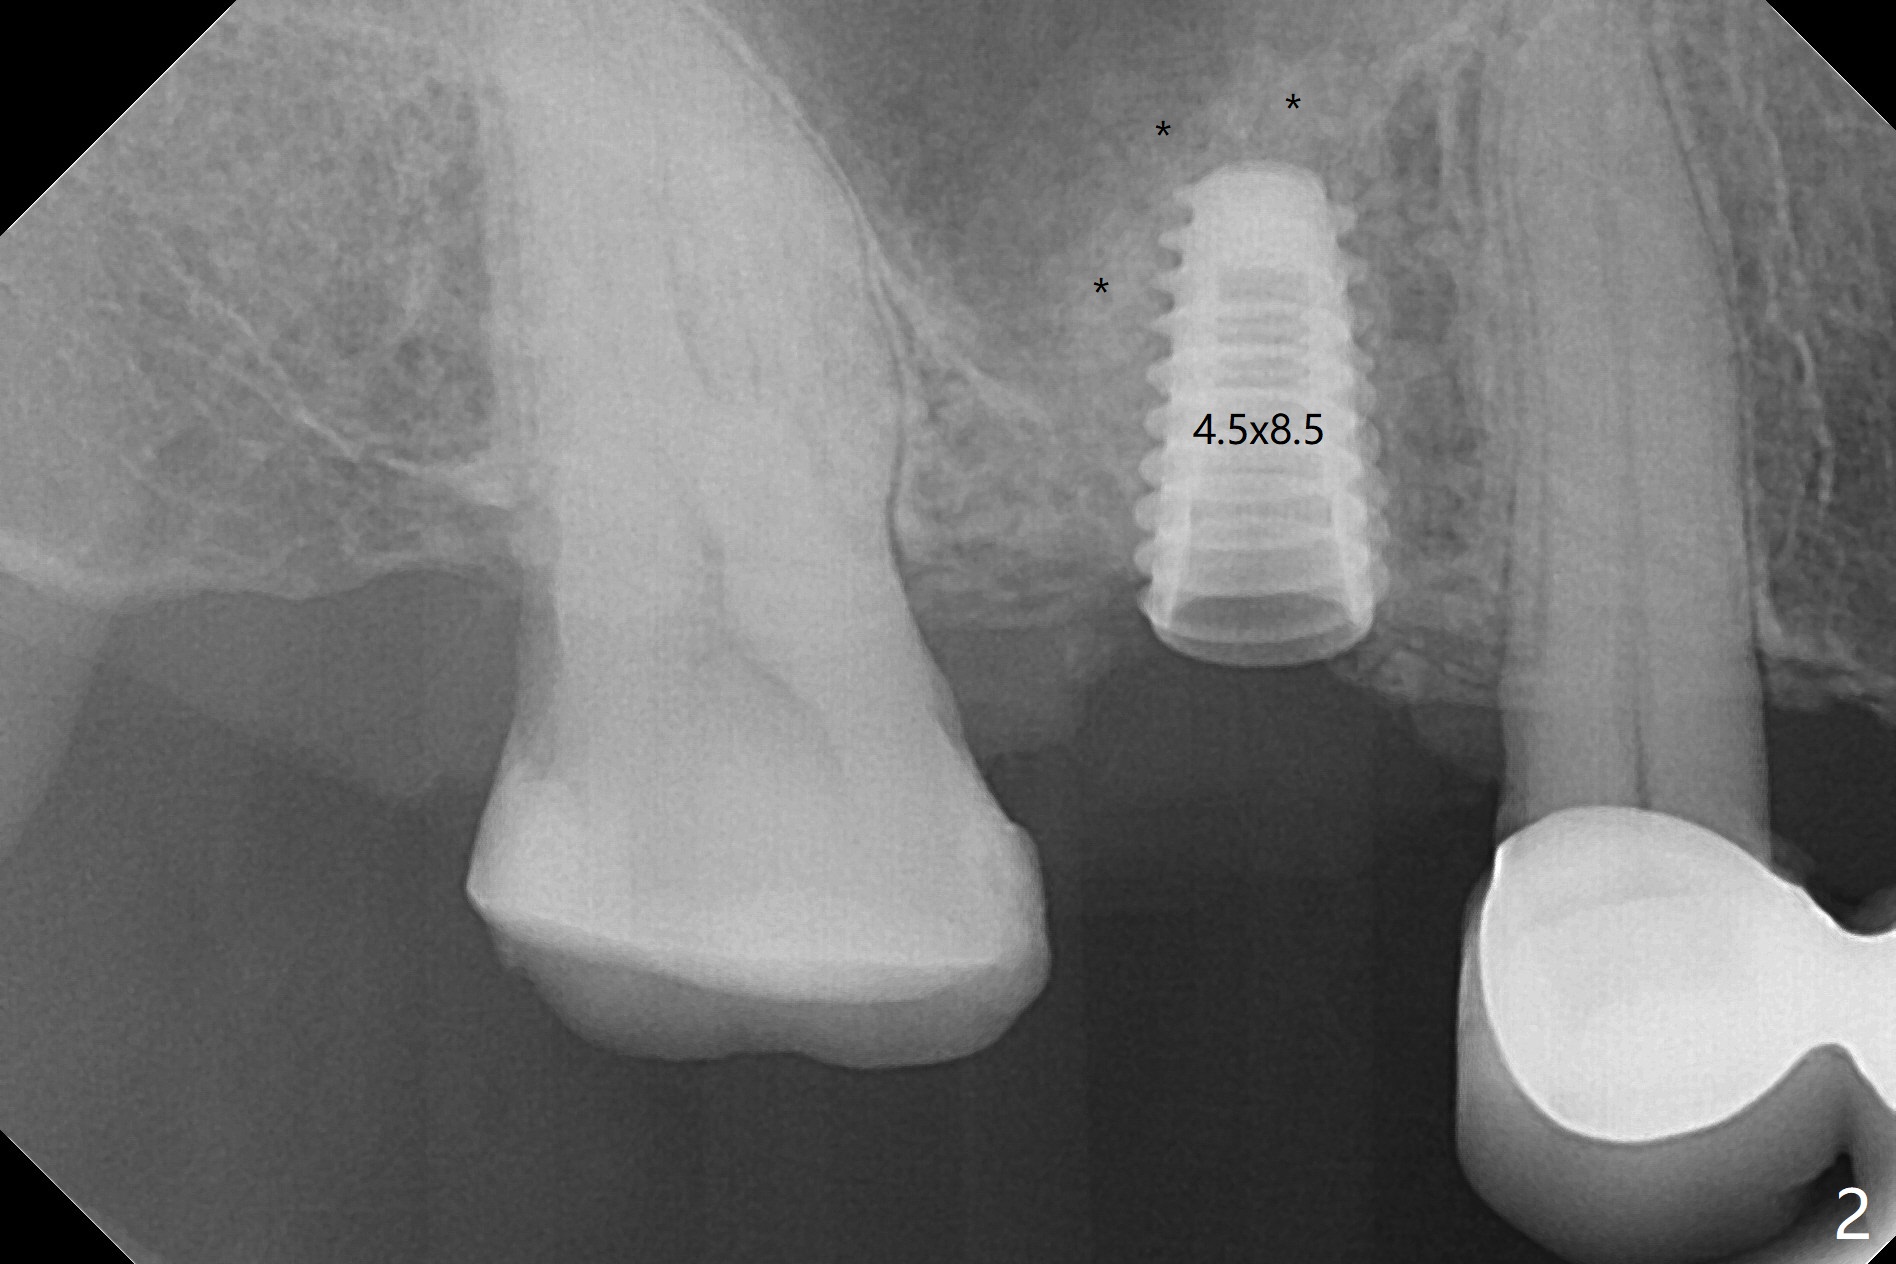

我们将使用粘性骨块做上颌窦内提升。抽血,一个红试管(含促凝剂),离心每分钟1500转,3分钟,提取上清液,与异体骨混合,几秒钟骨粉就开始凝聚(录像)。右上六缺牙区切开,开始用2毫米钻头钻洞,深度4毫米,如何使用2.8,3.6毫米园钻头(对上颌窦膜安全),4-6 毫米深,由于上颌窦底板是斜型,没有突破感。接着想利用粘性骨块和报废植体,把骨块送上去,这时骨块相当硬,必须事先剪成适当大小,然后用报废植体(4x10毫米)慢速推上去(录像2,图一(*骨块))。数次提升后,放置4.5x8.5毫米正式植体(图二),调整植体深度(图三:<),在稍微暴露植体表面放置骨块(图四:*)。其实愈合基台没有就位(图五:>),更换后没这个问题(图六)。